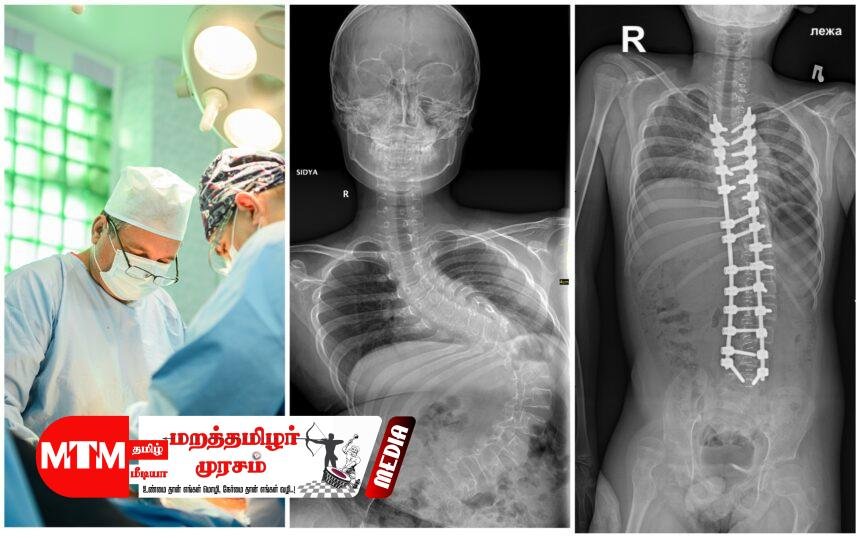

புத்தளம் தள வைத்தியசாலை வரலாற்றில் முன்னெப்போதும் இல்லாத வகையில், மிகவும் சிக்கலான முள்ளந்தண்டு நேராக்கல் (Scoliosis Correction) சத்திரசிகிச்சை அண்மையில் வெற்றிகரமாக முன்னெடுக்கப்பட்டது. இலங்கையின் ஒரு தள வைத்தியசாலையில் (Base Hospital) இச்சிகிச்சை இடம்பெற்ற முதலாவது சந்தர்ப்பம் இதுவாகும்.

கடந்த சில மாதங்களாகவே புத்தளம் தள வைத்தியசாலையில் பல்வேறு முள்ளந்தண்டு சத்திரசிகிச்சைகள் முன்னெடுக்கப்பட்டு வந்த போதிலும், முள்ளந்தண்டு வளைவைச் சீர்செய்யும் இந்த ‘Scoliosis Correction’ சிகிச்சை அங்கு இடம்பெற்றது இதுவே முதல் முறையாகும். பொதுவாக இச்சிகிச்சையானது கொழும்பு, கண்டி, யாழ்ப்பாணம், பதுளை மற்றும் இரத்தினபுரி போன்ற பிரதான போதனா வைத்தியசாலைகளில் மட்டுமே வழங்கப்பட்டு வந்தது. என்பு முறிவு விசேட வைத்திய நிபுணர் டாக்டர் ஷெஸார் ஹமீத் தலைமையில் இந்த அறுவை சிகிச்சை நடைபெற்றது. இவருடன் தேசிய வைத்தியசாலையின் சிரேஷ்ட என்பு முறிவு விசேட வைத்திய நிபுணர் டாக்டர் உதை டி சில்வா,

தனியார் மருத்துவமனைகளில் 40 இலட்சம் ரூபாவுக்கும் அதிக செலவு ஏற்படும் இந்த உயர்தர சிகிச்சை, புத்தளம் வைத்தியசாலையில் நோயாளிகளுக்கு முற்றிலும் இலவசமாக வழங்கப்பட்டுள்ளமை குறிப்பிடத்தக்கது.